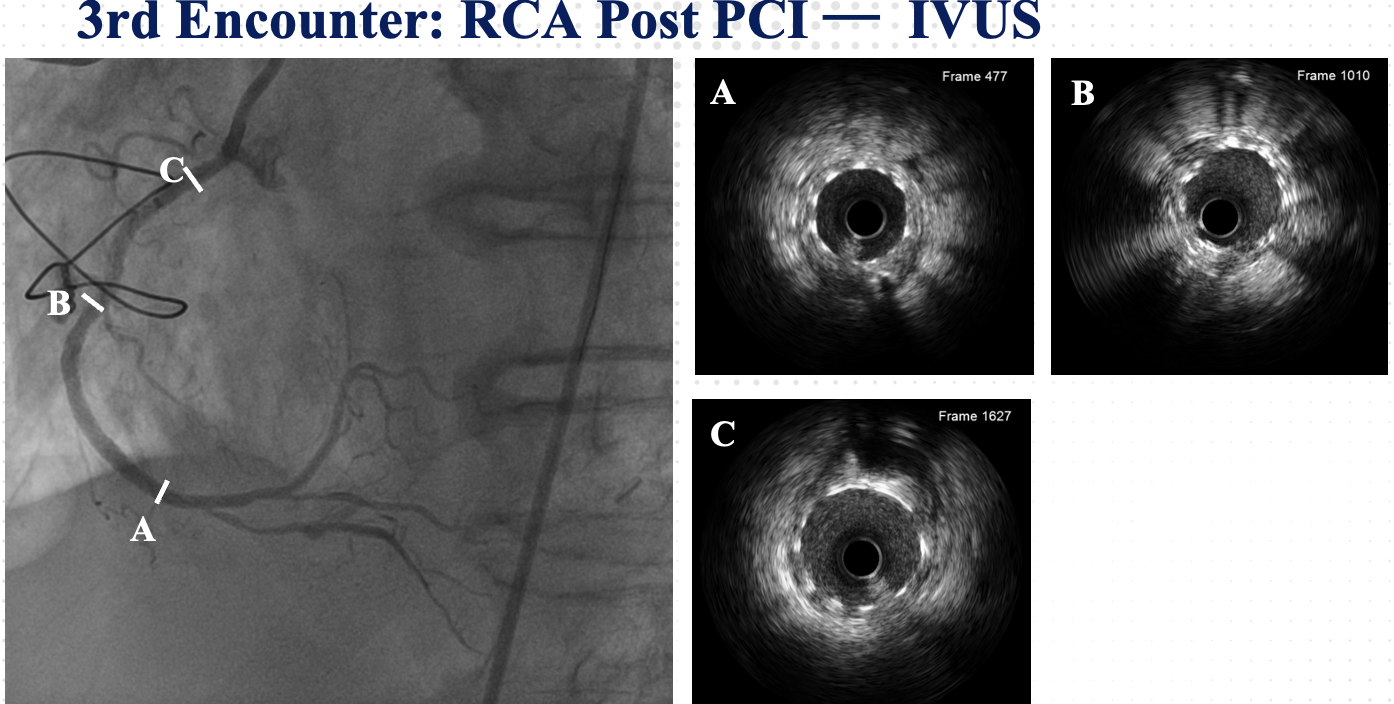

At the 1st encounter, RCA CTO PCI was performed with a plan for staged PCI of the left system. Using a 7F AL 0.75 for strong support, an antegrade approach with a double-lumen microcatheter and parallel wire technique (Pilot 150) successfully crossed the lesion. Predilatation with a 1.5 ¡¿ 15 mm balloon was done. IVUS could not pass due to 360¡Æ calcification. Rotablation with a 1.25 mm burr was attempted but limited to mid-RCA. Two DES were implanted from mid to proximal RCA, followed by post-dilatation.At the 2nd encounter, RCA stents were patent. PCI was done on LM, LAD, and D2. D2 was treated with DCB. LAD predilatation followed by OCT showed severe 330¡Æ calcification (max thickness 1.04 mm, MLA 1.63 mm©÷). IVL with a 2.75 ¡¿ 12 mm balloon (30 pulses) achieved multiple calcium fractures. A 2.75 ¡¿ 33 mm DES was deployed with good OCT results.At the 3rd encounter, 6 months later, the patient presented with ADHF. Angiography revealed RCA ISR CTO at the mid-bending site. The lesion was crossed with a Pilot 200 wire; predilatation showed a dog-bone sign. We do balloon based strategy for plaque modification using cutting, scoring, and double-wire balloons. IVUS showed stent underexpansion with 270¡Æ calcification and distal RCA stenosis. IVL with 2.5 and 2.75 mm balloons optimized the lesion, followed by two DES from distal to mid RCA. Post-PCI IVUS confirmed good result.